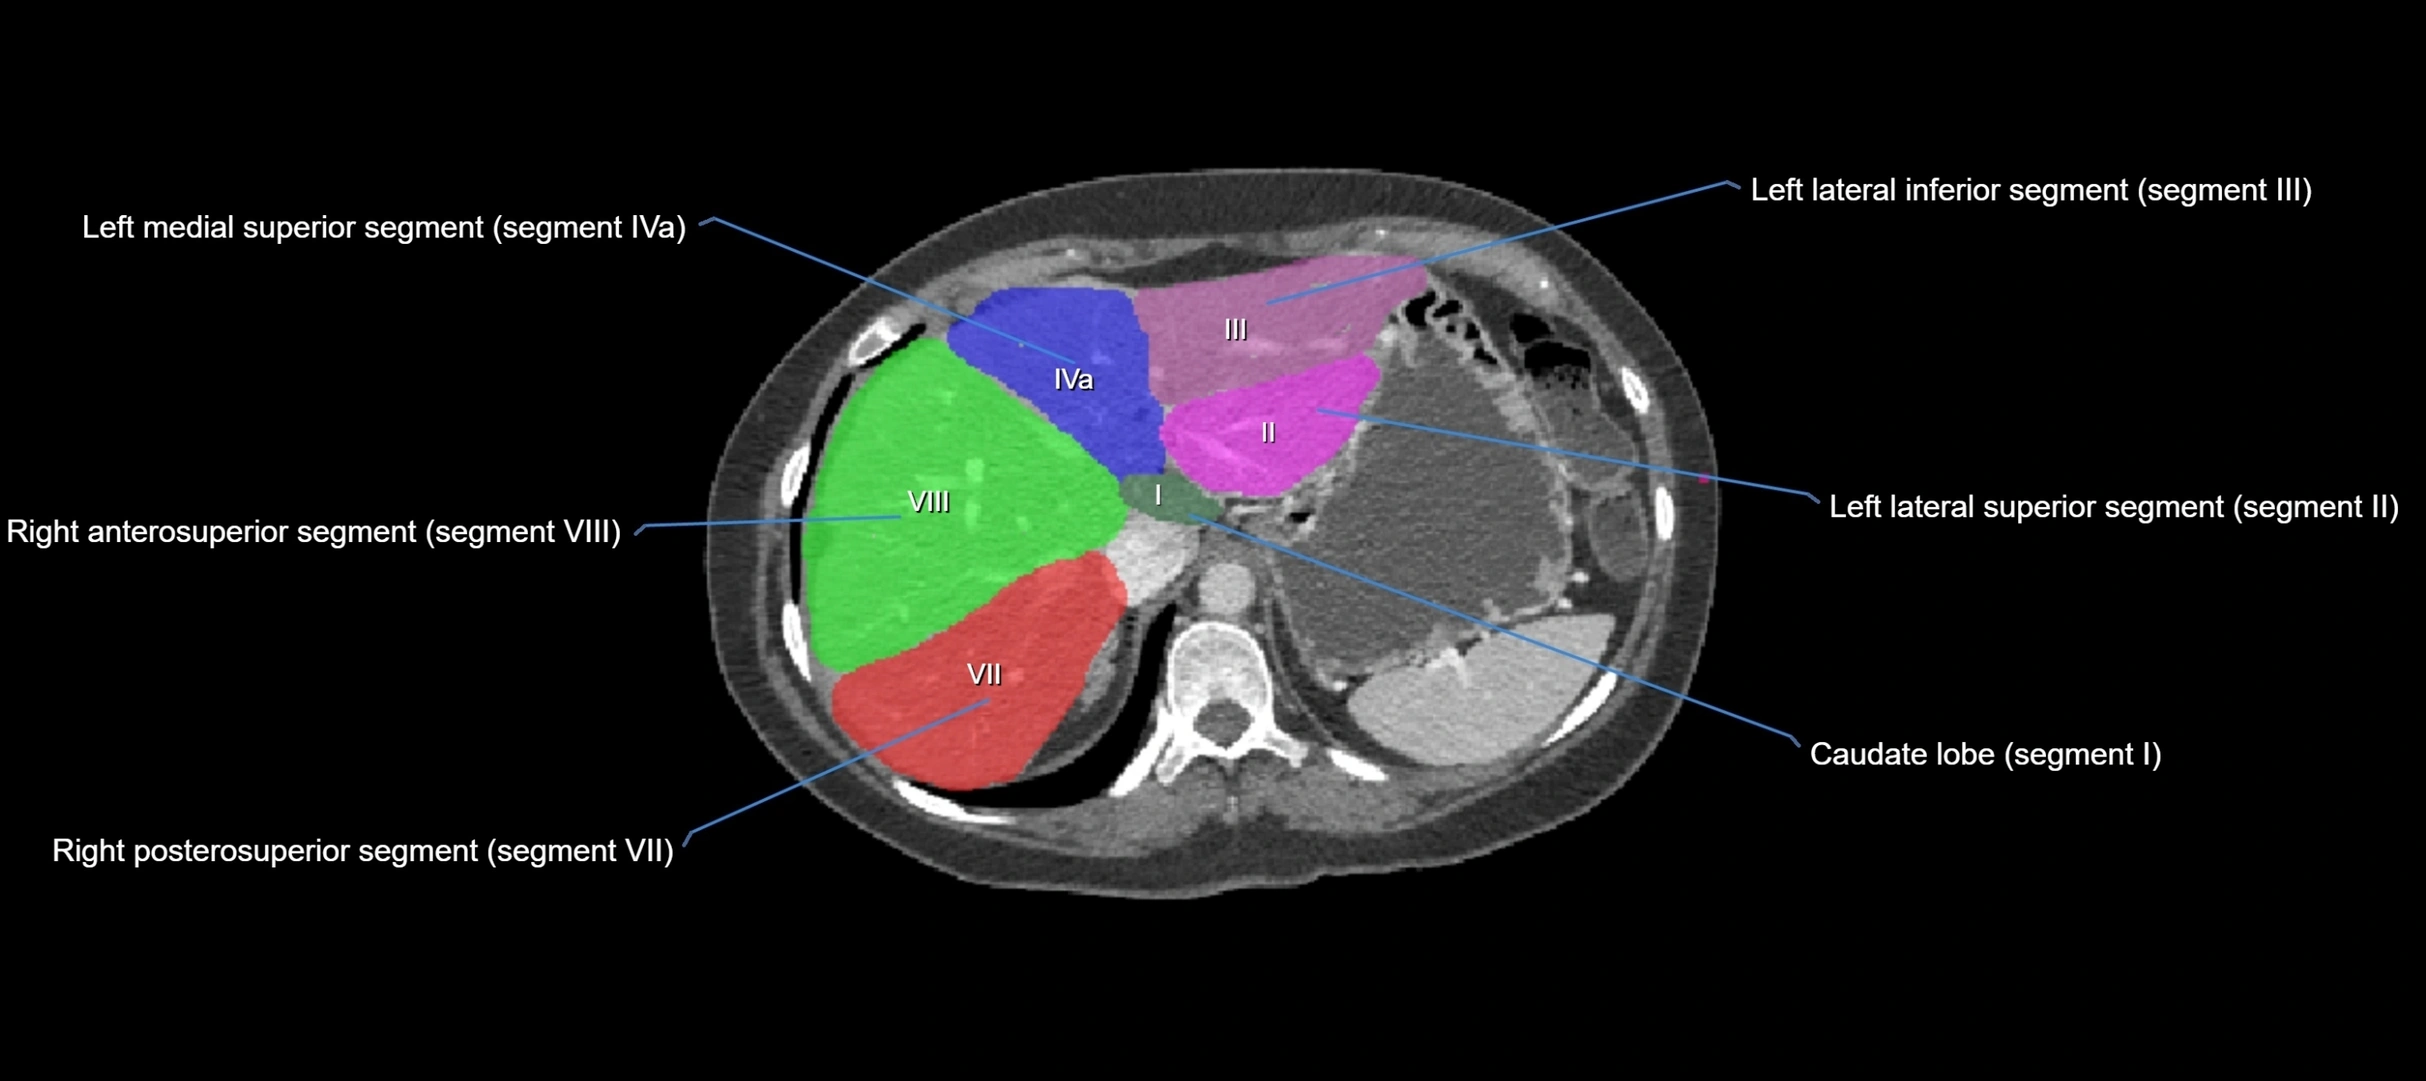

The caudate lobe of the liver is a distinct anatomical subdivision of the liver, designated as segment I in Couinaud’s classification. It lies on the posterior surface of the liver, between the fissure for the ligamentum venosum (left boundary) and the groove for the inferior vena cava (IVC) (right boundary). Superiorly, it is related to the posterior liver surface, and inferiorly it is separated from the left lobe by the porta hepatis.

The caudate lobe is unique because it receives dual portal venous and arterial inflow from both the right and left portal veins and hepatic arteries. It also has independent venous drainage directly into the IVC via multiple small hepatic veins, unlike other lobes that drain through the three main hepatic veins.

This anatomical autonomy makes the caudate lobe especially significant in liver surgery, transplantation, and hepatic venous outflow obstruction syndromes (e.g., Budd–Chiari syndrome). Enlargement of the caudate lobe is a characteristic imaging feature in chronic liver disease and cirrhosis.

CT Appearance

CT Pre-Contrast:

• Caudate lobe appears as a soft-tissue density, isodense to the rest of the liver

• Enlargement may be appreciated in cirrhosis or Budd–Chiari syndrome

CT Post-Contrast:

• Homogeneous enhancement in the portal venous phase, similar to rest of liver

• Independent venous drainage into the IVC may be visualized

• Lesions follow characteristic CT enhancement patterns (HCC: arterial hyperenhancement with washout; hemangiomas: peripheral nodular enhancement with centripetal fill-in)

CT Venous Phase (functional significance):

• Caudate lobe often enhances relatively more than other lobes in Budd–Chiari syndrome, due to preserved venous outflow

CT Image

image